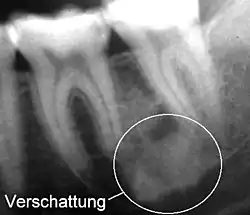

Verschattung

Eine Verschattung (auch Radioopazität) ist ein heller und eine Aufhellung (Radioluzenz) ein dunkler Bereich auf einem Röntgenbild.[1] Grund ist die unterschiedliche Röntgenopazität von Gewebearten.

Da die Begriffe aus der Ära des Fluoreszenzradiographie beibehalten wurden, liegt ein scheinbares Paradoxon vor. Es wird also ein Bereich auf dem Röntgenfilm, der heller ist, als er sein sollte, verschattet genannt und ein Bereich, der dunkler ist, als er sein sollte, aufgehellt genannt.